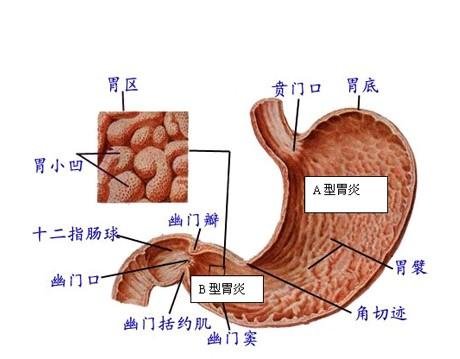

导读 萎缩性胃炎是胃黏膜呈慢性浅表性炎症的疾病,为消化系统常见病,属慢

导语 萎缩性胃炎也称慢性萎缩性胃炎,以胃黏膜上皮和腺体萎缩,数目减少,